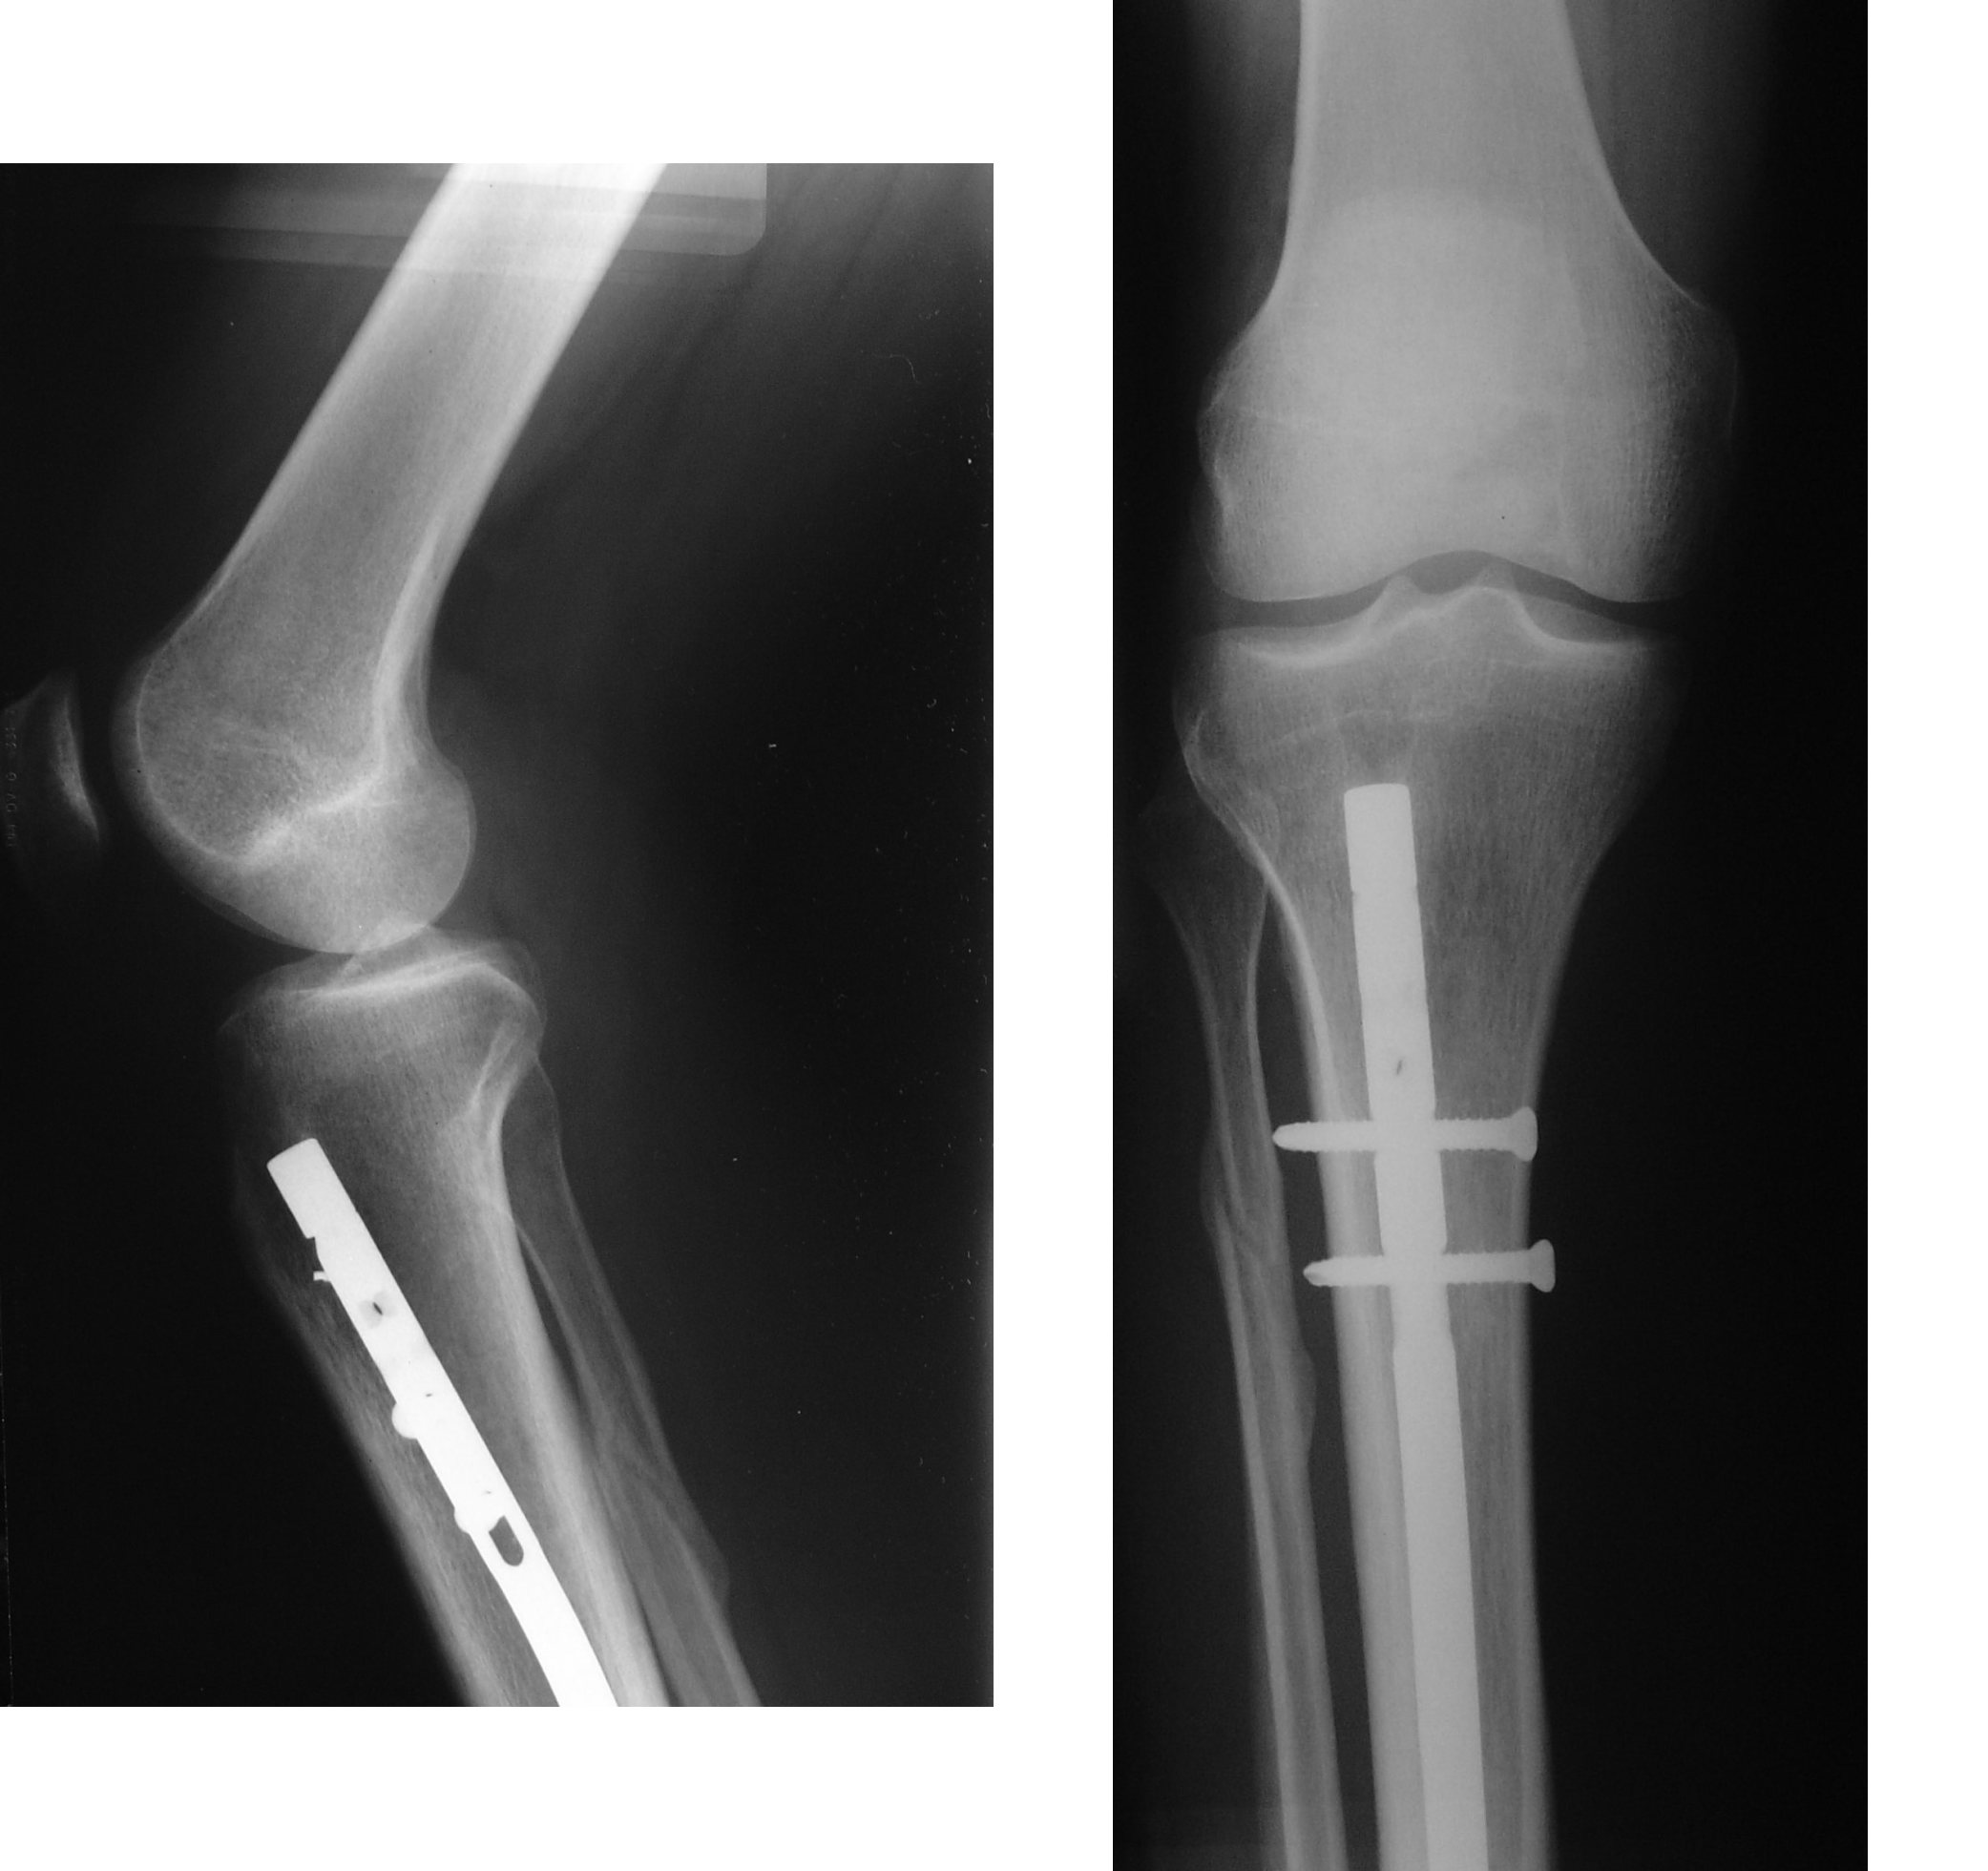

These are metal rods inserted into the medullary canal of long bones, such as the femur or tibia. They provide stability along the length of the bone.

Intramedullary Fixation

This involves using an intramedullary nail or rod inserted into the marrow cavity of the bone. It is often used for long bone fractures.